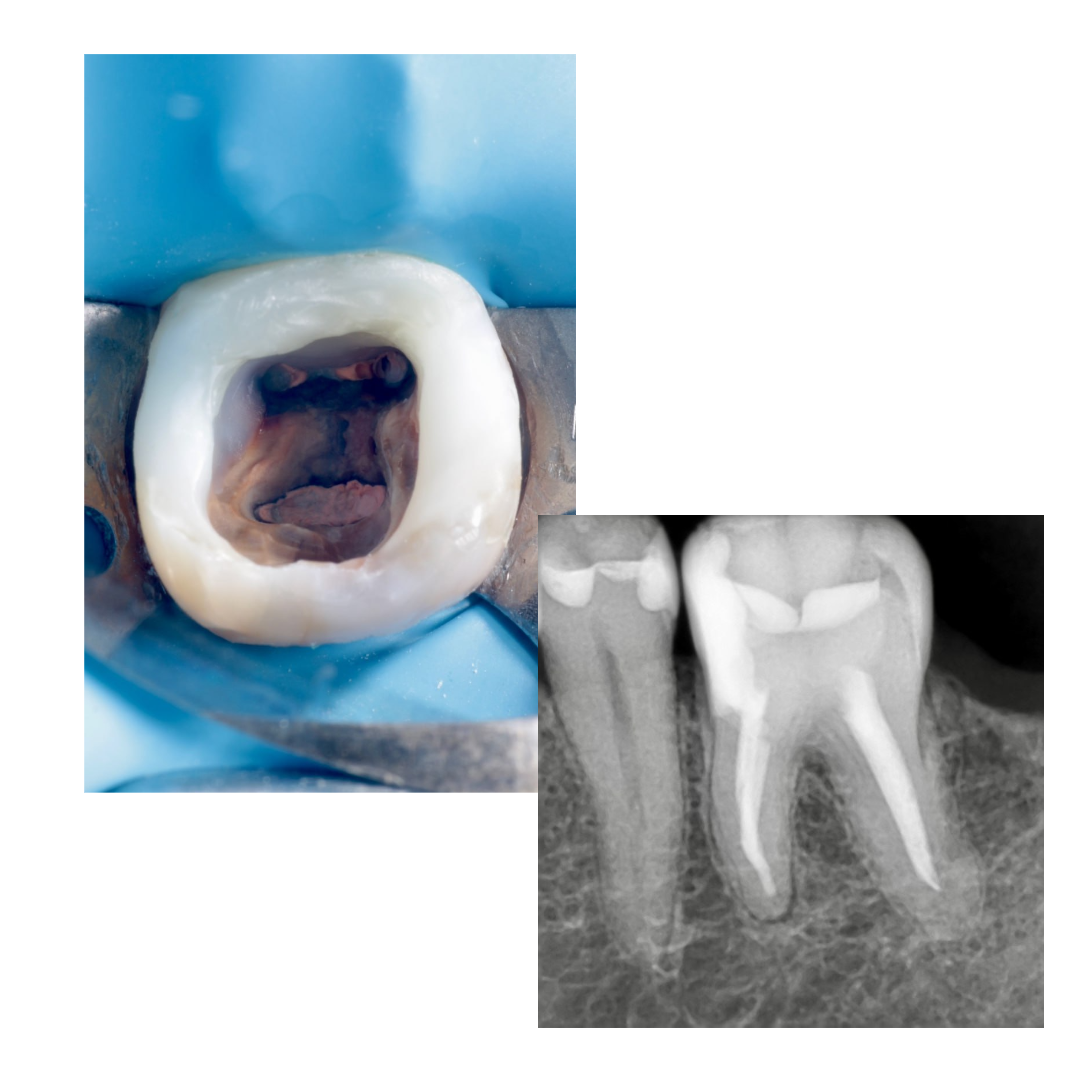

🔹Внутри небольшое воспаление, изначально хотел вообще каналы не перелечивать, но потом передо мной открылся шикарный вид пульповой камеры.

🔹Почистил, отпесочил, понял что можно восстановить. Но из-за инвагинации стенки, решил вот так заморочиться с клином (воткнуть вертикально и зафиксировать)

🔹Щечную и язычную стенку доделал фрихендом. На следующий визит, распломбировка цемента и перепломбировка : биокерамика + непрерывная волна